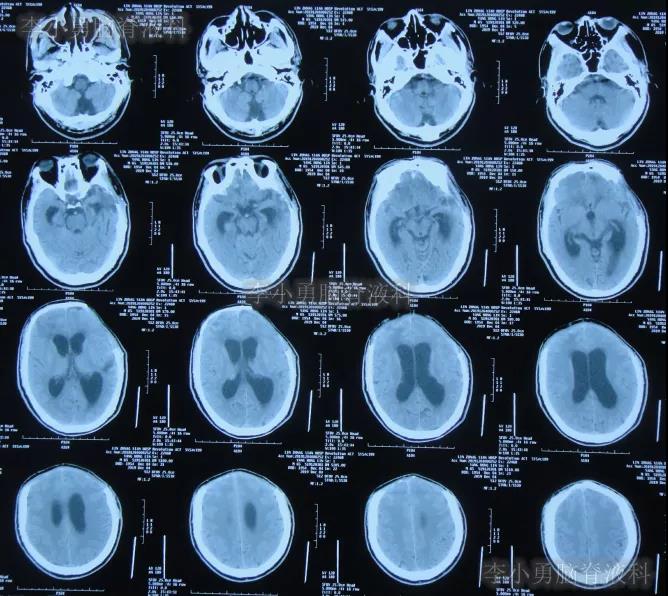

为求进一步有效治疗,于第1家医院出院后19天即2019年12月10日,住入第2家的北京某解放军的三甲医院,入院次日查头颅CT(图-14)后认为是脑积水。

图-14:2019年12月11日头颅CT

图-15:2019年12月16日头颅CT

颅骨修补术+脑室腹腔分流术后第6天即2019年12月19日,复查头颅CT示引流管周围少量出血(图-16),给予拔除头部引流,换做腰大池引流。

图-16:2019年12月19日头颅CT

腰大池引流术后5天即2019年12月24日(颅骨修补术后11天即拔除脑室引流管后5天),查头颅CT示脑室仍扩张(图-17)。

图-17:2019年12月24日头颅CT